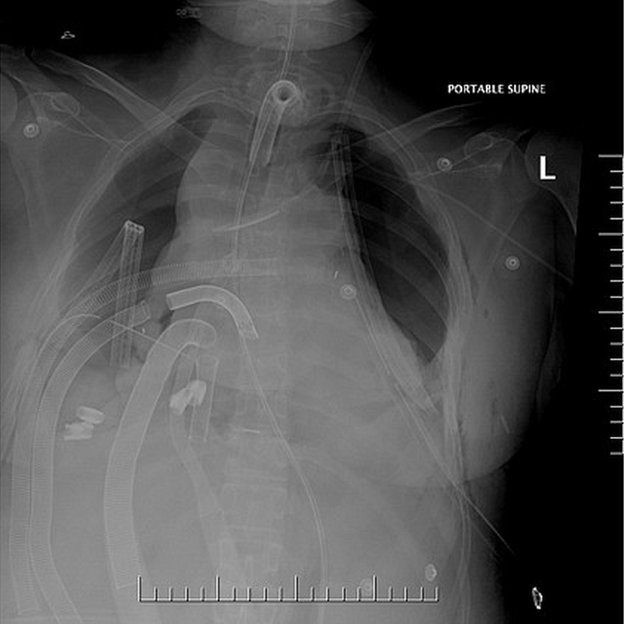

Este es el diagrama del soporte mecánico antes del trasplante, mientras no tenía pulmones que los doctores incluyeron en el informe publicado en el Journal of Thoracic and Cardiovascular Surgery.

Tras la neumonectomía bilateral para tratar shock séptimo pulmonar.

Le conectaron un pequeño pulmón artificial al corazón mientras que otros aparatos oxigenaban y se encargaban de la circulación de su sangre.